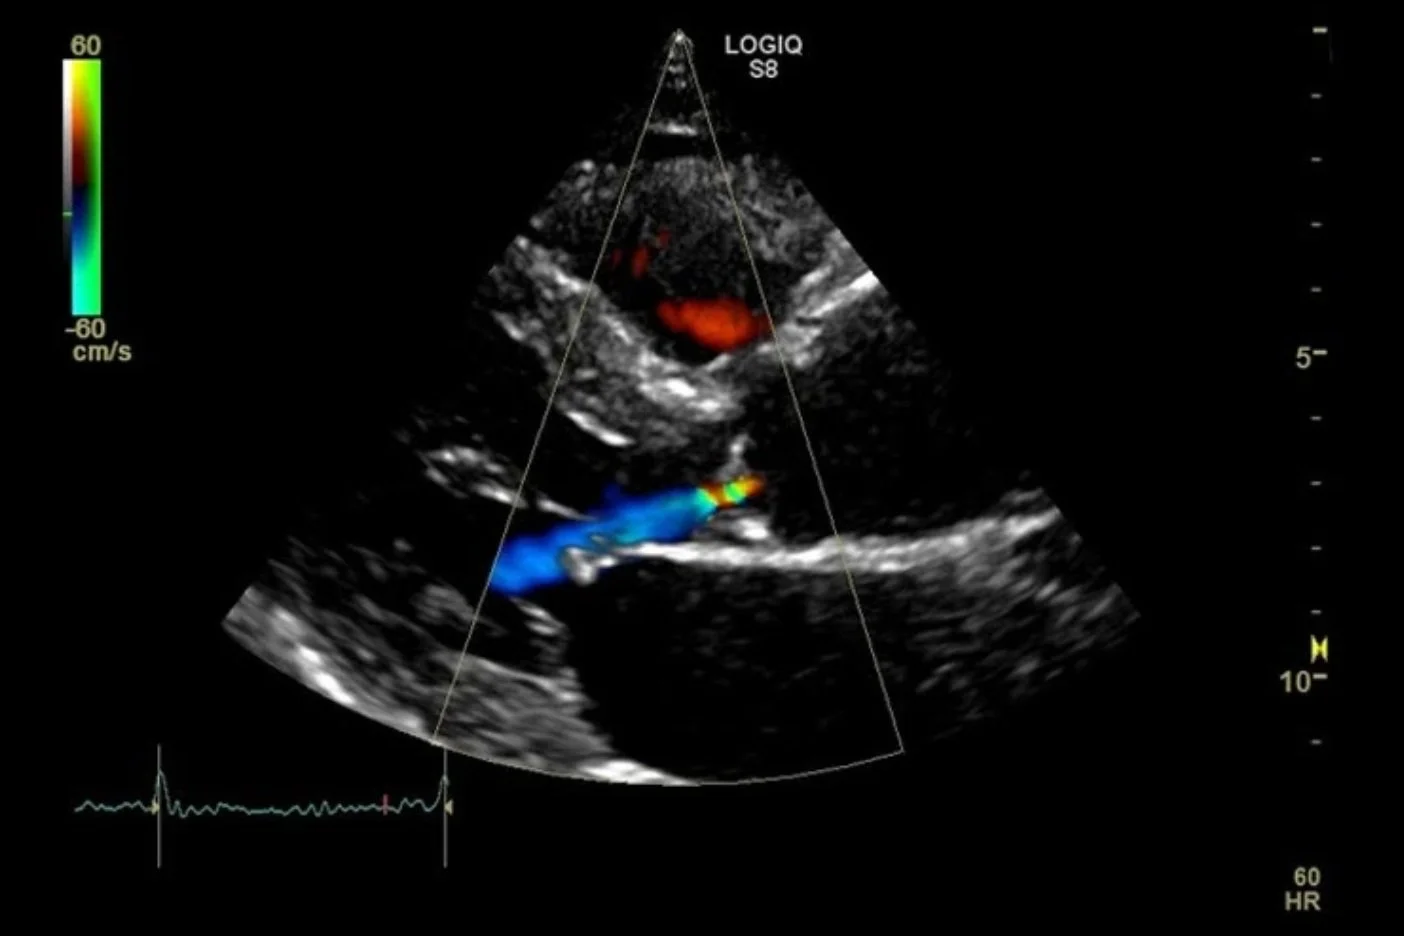

Vascular/Echocardiogram